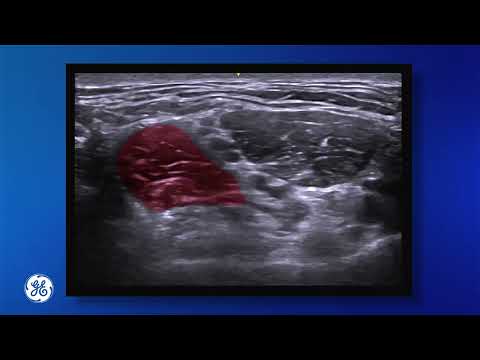

Supraclavicular Brachial Plexus Block

Ultrasound guided supraclavicular brachial plexus block